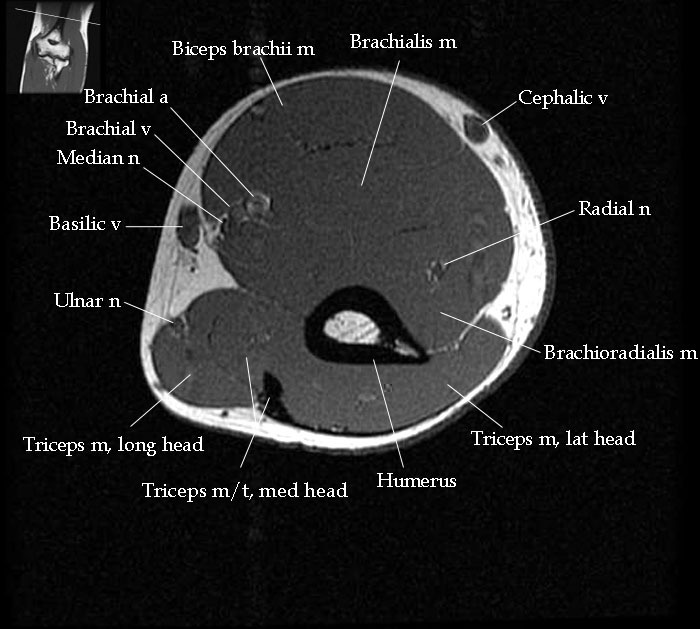

elbow anatomy